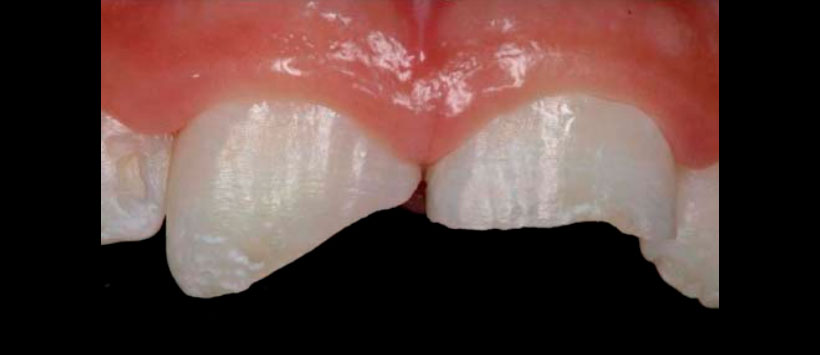

La necrosis pulpar en dientes con ápice abierto representa un desafío al tratamiento endodóntico. Esto debido a que la anatomía radicular se encuentra parcialmente formada, con ápices abiertos, paredes radiculares finas y frágiles, así como la longitud radicular reducida.

En estas situaciones, cuatro opciones de tratamiento están disponibles: 1) Apexificación con renovación periódica de medicación intraconducto (MIC), hasta que sea posible observarradiográfi camente el cierre apical; 2) Apexificación sin renovación de MIC; 3) Confección de una barrera apical utilizando agregado de trióxido mineral (MTA) o Biodentine; 4) Revascularización pulpar.

Este artículo llevó a cabo una revisión de la literatura sobre las diferentes formas de tratamiento en casos de dientes traumatizados con rizogénesis incompleta y necesidad de tratamiento endodóntico por necrosis pulpar, indicando las ventajas, desventajas y limitaciones de cada una basado en el análisis de los estudios imagenológicos antes y después del tratamiento. (Figura 2)